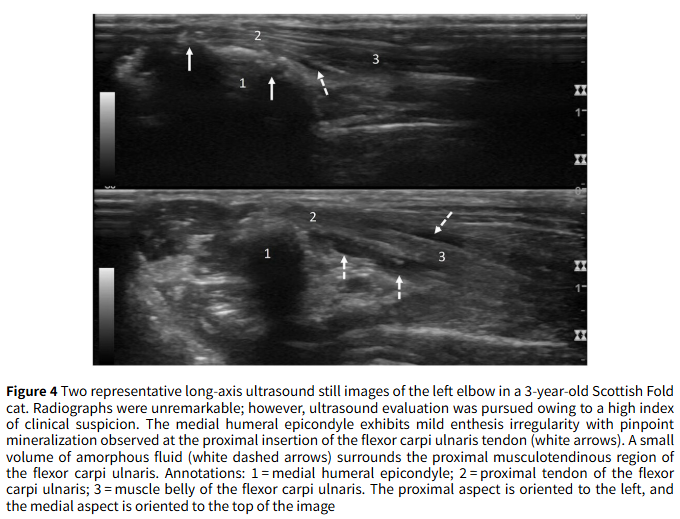

- 결과 2: 영상 진단의 유용성 방사선 검사만으로는 질병의 전체적인 상태를 파악하기 어려웠습니다. CT 촬영을 진행한 10개의 팔꿈치 중 7개에서 방사선으로는 확인되지 않았던 추가적인 문제, 특히 **관절 내 유리체(mineralized bodies)**가 5개의 팔꿈치에서 발견되었습니다. 또한, 방사선 소견이 경미했던 4개의 팔꿈치에 대해 초음파 검사를 시행한 결과, 힘줄 주변의 미세한 염증과 초기 단계의 광물 침착을 발견할 수 있어 조기 진단에 대한 초음파의 가능성을 확인했습니다.

셋째, 진단 도구의 활용에 대한 중요한 관점을 제시합니다. 방사선에서 광물 침착이 뚜렷해졌을 때는 이미 비수술적 치료의 효과가 떨어지는 만성 단계일 수 있습니다. 따라서 임상 증상이 의심될 경우, 초음파와 같은 정밀 영상 검사를 통한 조기 진단이 비수술적 치료의 성공률을 높일 수 있습니다. CT 검사는 수술이 필요한 경우, 관절 내 유리체 존재 여부를 확인하여 수술 계획을 세우는 데 필수적입니다.